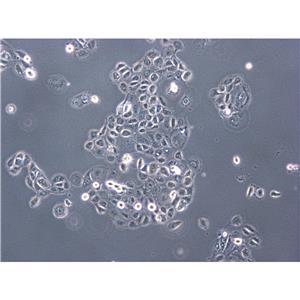

"MNNG/HOS Cells人骨肉瘤细胞系(提供STR图谱)

" "传代比例:1:2-1:4(首次传代建议1:2)

" "背景信息:骨肉瘤;女性

" "换液周期:每周2-3次

" "生长特性:贴壁

" "MNNG/HOS Cells人骨肉瘤细胞系(提供STR图谱)

" "形态特性:详见细胞说明书

" "MNNG/HOS Cells人骨肉瘤细胞系(提供STR图谱)

" "MNNG/HOS Cells人骨肉瘤细胞系